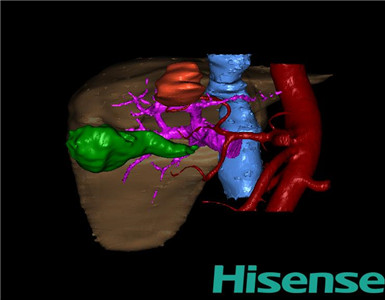

术前三维重建及手术方案设计:

将0.625mm双源薄层CT资料的静脉期和动脉期Dicom格式文件导入海信CAS系统。

通过调节窗宽窗位调整CT序号,对肿瘤,肝实质,胆囊,下腔静脉,肿瘤,肝动脉、门静脉及肝静脉等进行三维重建;系统自动计算肿瘤体积和肝脏体积。(模拟手术操作,自动计算切除肿瘤体积。术前手术方案的规划。

术前三维重建:

重建图片